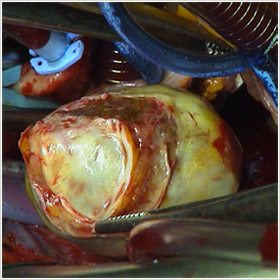

Le myxome est situé le plus fréquemment dans l’oreillette gauche (75 à 90 % des myxomes).

Les myxomes de l’oreillette gauche (O.G) sont des tumeurs bénignes du point de vue anatomo-pathologique mais de par leurs conséquences (embolies, enclavement dans l’orifice mitral), ces tumeurs peuvent mettre en jeu le pronostic vital.

La clef du diagnostic de myxome comme des autres tumeurs cardiaques est l’échographie cardiaque qui va révéler la tumeur et sa localisation. L’échocardiographie apprécie la taille, la forme, la structure, la mobilité et la zone d’insertion du pédicule de cette tumeur.

Sous circulation extracorporelle, le cœur et les poumons sont arrêtés. On ouvre l’oreillette gauche et on procède à l’ablation de l’intégralité de la tumeur sans la fractionner. On résèque la zone d’implantation qui siège le plus souvent au niveau de la cloison entre les deux oreillettes et qui est refermée par un patch de péricarde ou de Dacron.

On explore les quatre cavités cardiaques, oreillettes et ventricules à la recherche d’une autre localisation tumorale. On explore aussi les valves cardiaques qui peuvent avoir été lésées par les mouvements de la tumeur.